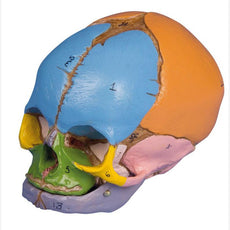

The calvarium is sectioned horizontally leaving the temporal bone and its sutures intact. Bony impressions of the superior sagittal sinus, transverse sinus and sigmoid sinus as well as the meningeal vessels have been painted. The base portion of the skull has been sagittaly sectioned in the way that it passes through the one cribriform plate on one side and another section in the same plane passes through the other cribriform plate of the ethmoid leaving the crista galli perpendicular plate of the ethmoid intact as also the whole nasal septum.

The structures of anterior, middle and posterior cranial fossae are easily accessible. One can directly visualize the nasal cavity, the concha, the nasal septum, the bony pharyngeal and naso-pharyngeal spaces. The nasal septum is separable from surrounding bones. The frontal sinuses have been dissected on one side to show the sinus as whole and on the other side chiselled out for full access to the sinus. The relation of this sinus to the nasal cavity is clearly shown and is especially valuable for otolaryngologists.

On one side of the skull the temporal bone has been left in situ. The other temporal bone is removable from the skull. A portion of the mastoid and squama can be removed along with the tympanic antrum, baring internal ear in full view. All three semicircular canals are visible along with the course of the facial nerve coursing backwards and then downwards emerging finally through the stylo-mastoid foramen. The removable temporal bone has the external auditory meatus intact.

An almost vertical section through the squama mastoid process and carried inwards along the petro-squamosal junction has been made and when apart, one sees the position of tympanic membrane. The carotid canal has been opened as also the cochlea , showing the internal canal, and the course of the facial nerve has been depicted. Oval window, the semi-circular canals, and aditus of the tympanic antrum are visible.

The maxilla and mandible expose the structures of dentition, the roots, the bony margin of the alveolar process, dental vessels and nerves are visible. The maxillary sinus can by opened by removing a bone flap. Teeth of the right mandible are sectioned to show the inner tooth structure.